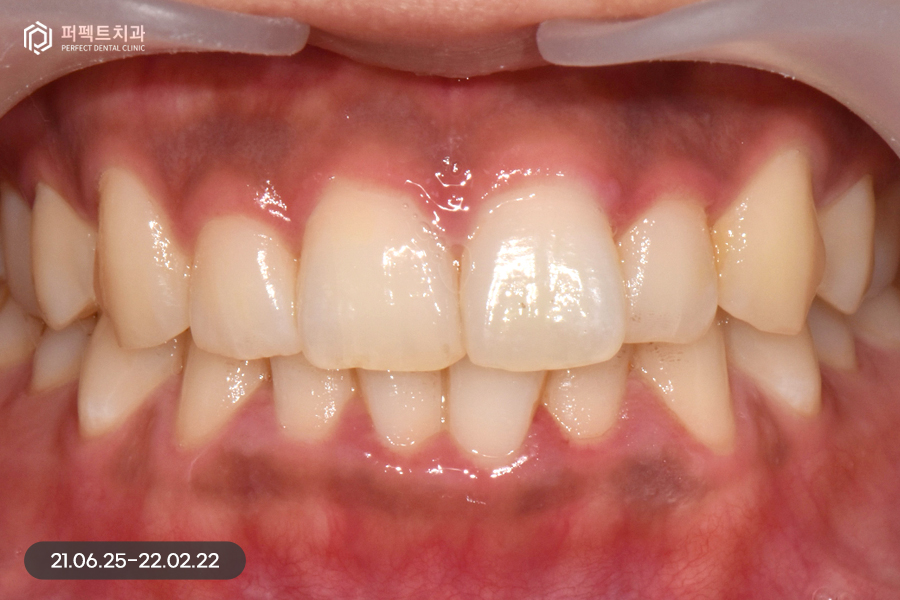

사진으로 보았을 때 큰 문제가 없어보이지만 실제로는 위 아래 치열이 삐뚤빼뚤하고 아래 치아의 경우 위 치아보다 더 틀어짐이 심했는데요. 그렇기 때문에 부분교정을 5개월 정도 진행하였습니다.

교정 후 치아가 가지런하게 펴졌는데, 교정을 하면 항상 생기는 문제점 중 하나가 바로 고르지 못한 치아들이 가지런하게 펴지면서 잇몸 사이 공간인 블랙트라이앵글입니다.

위 환자분도 마찬가지로 블랙트라이앵글이 발생했고, 이 공간을 해결함과 동시에 치아 색상도 하얗게 변화를 주길 원하셨습니다. 그렇기 때문에 위, 아래 6개 치아를 라미네이트 진행하였습니다.